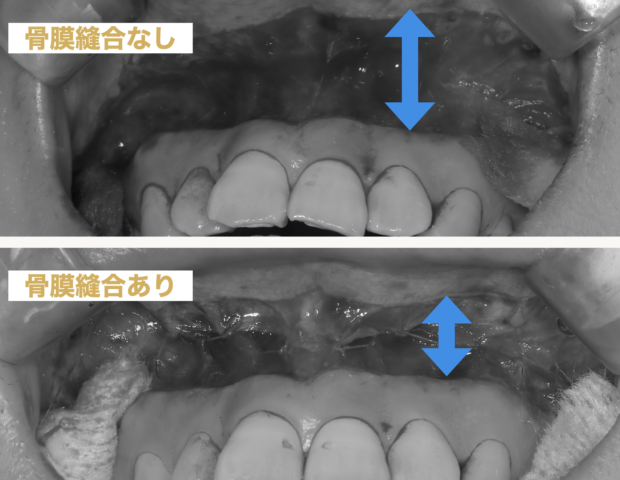

リップリポジショニングの後戻りを防ぐ骨膜縫合

2024年の9月から内側の骨膜を二重で縫合することで内側からも唇を上らないようにします。この方法により圧倒的に後戻りしにくくなりました!

最新の二重縫合

骨膜縫合と従来の縫合の二重縫合で後戻りを防ぎます。

最新の二重縫合でのリップリポジショニングを治療できるのは日本では現時点では本町ノーブル歯科 矯正歯科だけ!